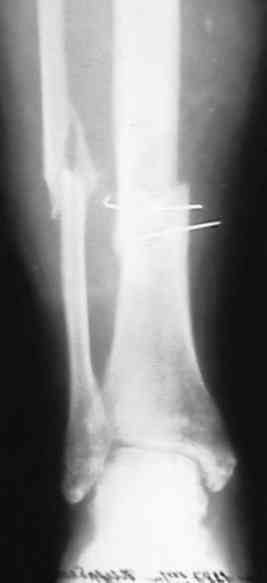

поступил больной с замедленной консолидацией перелома голени . Травма ДТП 15 мая 2007года (6 мес. Назад) . Первичный диагноз : открытый перелом голени 2 А степени (Каплан-Маркова) . В одной из районных больниц выполнена трансфиксация , я так понимаю , по Паппу спицами и наложена гипсовая повязка . .Затем больной находился под наблюдением травматолога поликлиники , Свищей , длительно незаживающих ран , вроде (со слов больного) не было . ВТЭК, 2 группа . Но больной хочет ходить , (вроде нормальное желание ) На сегодняшний день имеем вот такую картинку (см. . Снимки) Анализы абсолютно нормальные . Температура 36,6 в течении суток . Клинически : отёк голени , движения в КС и голеностопном суставе практически в полном объёме . В зоне перелома определяется безболезненная подвижность , опора на конечность невозможна . PLS !!!подскажите , тактику лечения!Мой план : АВФ (БИОС недоступен) .Предполагаемый план операции: Проксимально стержень , дистально спица во фронтальной плоскости с учётом смещения . Парафрактурно оставляю <пустые> кольца . Открываю зону перелома и удаляю спицы . Остеотомия малоберцевой кости . Дистракция . В ране иссекаю межотломковую рубцовую ткань . Вскрываю костномозговые каналы . Восстановление длины и оси . Если получится ,то одномоментно . Если не нарвусь на гнойный очаг в области перелома , выполняю декортикацию . Возможно с применением аутотрансплантанта из крыла. Провожу репонирующие спицы ,стабилизирую АВФ . При наличии гнойного очага - то же самое + дебридмент , но без костной пластики и декортикации . Затем ,при благоприятном течении раневого процесса , ранняя нагрузка . При наличии проблем - ограничение нагрузки до санации раны , <аккордеонная техника> (по Голяховскому) . Прошу , выскажите замечания по технике и тактике лечения .С уважением Д.Б.

Мы бы убрали спицы через проколы кожи, по возможности. Затем аппаратом бы дозированно восстановили длину и ось. После этого закрыто

заштифтовали. Там по виду тугой ложный сустав, на дистракцию они обычно хорошо откликаются регенератом.